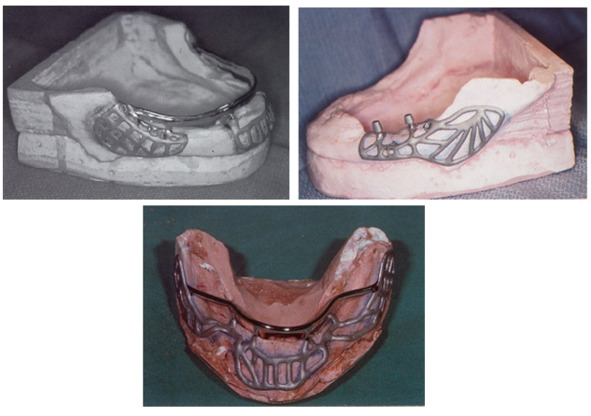

1937 году др. Мюллер (Muller) предложил субпериостальный имплантат из иридий-платина-золотого сплава.

1950—1960 годы становятся популярны субпериостальные имплантаты. Основной областью применения таких имплантатов стали челюсть с полной адентией и высокой степенью атрофии костной ткани.